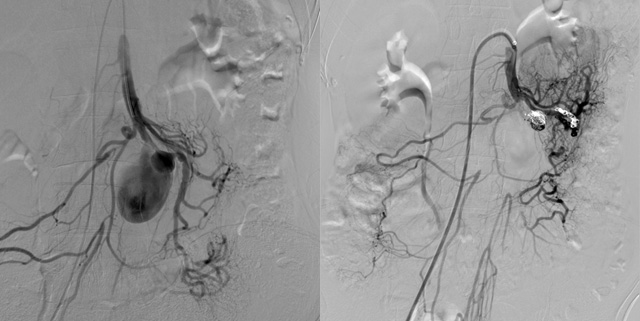

ENDOVASCULAR MANAGEMENT OF ACUTE GASTROINTESTINAL BLEEDING

The role of interventional radiology becomes vital in patients whose GIB remains resistant to medical and endoscopic treatment. Radiology offers diagnostic imaging studies and endovascular therapeutic interventions that can be performed promptly and effectively with successful outcomes.

Computed tomography angiography and nuclear scintigraphy can localize the source of bleeding and provide essential information for the interventional radiologist to guide therapeutic management with endovascular angiography and transcatheter embolization.